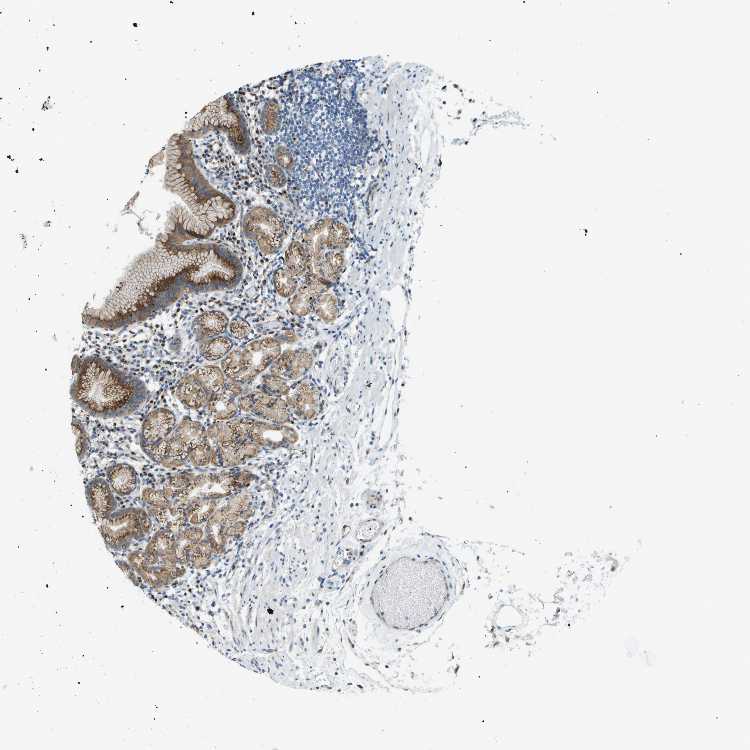

TISSUE PRIMARY DATA STOMACH Show tissue menu

STOMACH 1 - Antibody stainingi

Antibody staining in the annotated cell types in the current human tissue is reported as not detected, low, medium, or high, based on conventional immunohistochemistry profiling in selected tissues. This score is based on the combination of the staining intensity and fraction of stained cells.

Each image is clickable and will lead to virtual microscopy that enables deeper exploration of all samples and also displays staining intensity scores, fraction scores and subcellular localization as well as patient and tissue information for each sample.

Antibody HPA015594

Glandular cells Medium